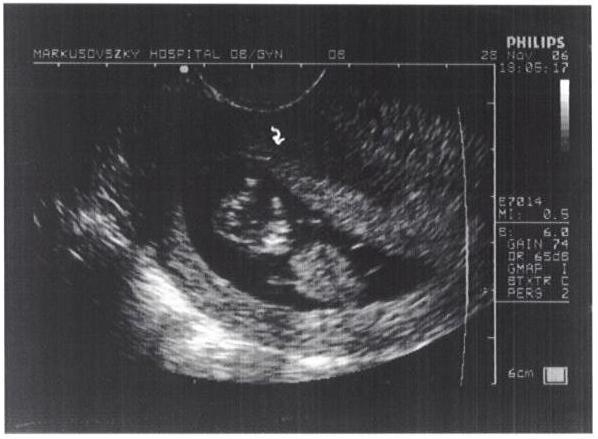

Volt HSG: eléggé fájt, de hősiesen viseltem. Semmi nincs zárva. Azt monta a doki nagyon szép minden.

Aztán volt hormon is: nem tudom emlékeztek e, de minden bizadalmam abban volt, hogy ott lesz a bibi. Hát nem. Ott is minden ok.

Meg volt PCT: azt mondta a doki, hogy ebből semmit nem tud megállapítani, egy két mozdulatlant látott, szerintem kifolyt belőlem minden

. Most úgy gondolom itt a bibi, de nem tuti.

Mehettünk volna inszemre (arra legalább jók vagyunk), de úgy dönöttünk hogy kicsi szünet, aztán folytatjuk. Ráadásul nem is a Kaáliban akarom csináltatni, mert nem olyan normálisak mint amennyit fizetni kell. Inkább keresek valami Tb-s dokit. De ez még majd kiderül.